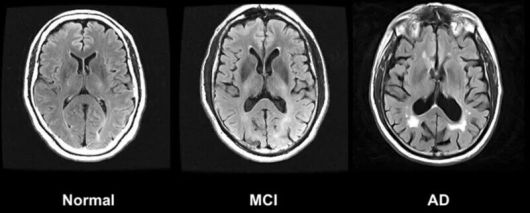

왼쪽부터 정상인, 경도인지장애(MCI), 알츠하이머병(AD)의 뇌. 위키미디어 코먼스 |